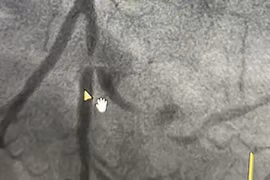

Đau ngực dữ dội... coi chừng bị nhồi máu cơ tim

Nhồi máu cơ tim gây những cơn đau thắt ngực, sau đó là hoại tử cơ tim dẫn đến suy tim hoặc đột tử.